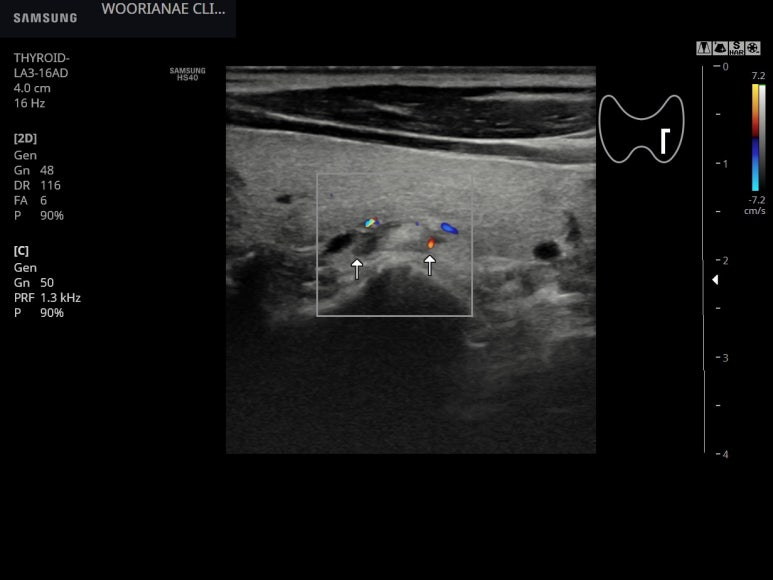

놓치기 쉬운 모양인데 갑상선 실질과 비슷한 음영의 결절이 갑상선의 후면에 위치하고

주변에 저음영이 있어 경계는 구별되나 전체적으로 고음영은 일반적인 부갑상선의 모습은 아닐수 있다.

; 같은 모습, parathyroid lipoadenoma